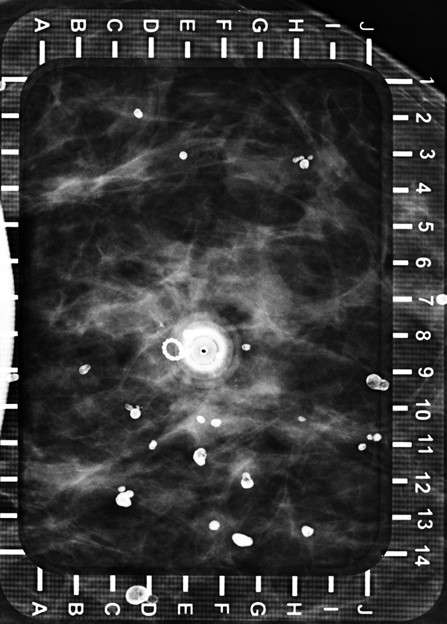

Radiologist advances the hollow needle perpendicular to the skin at the previously identified coordinates, to its full length or just above the detector on the far side of the breast.

Technologist obtains image to confirm location of needle over targeted lesion (within 0.5 cm) (Figure 2).